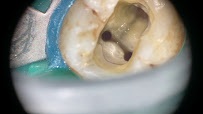

• Root Canal Treatment โ€“ Endodontic therapy to preserve infected or decayed teeth and restore function and comfort.

M Dental Clinic in Petaling Jaya is equipped with advanced dental technologies including dental microscopes, digital X-ray systems, and laser machines that enable precise, efficient treatment delivery. These modern tools allow the dentists at M Dental Clinic to visualize details, plan treatments accurately, and execute procedures with exceptional precision. The laser technology available at M Dental Clinic in Petaling Jaya enables minimally invasive treatment of various conditions while reducing patient discomfort and supporting faster healing.